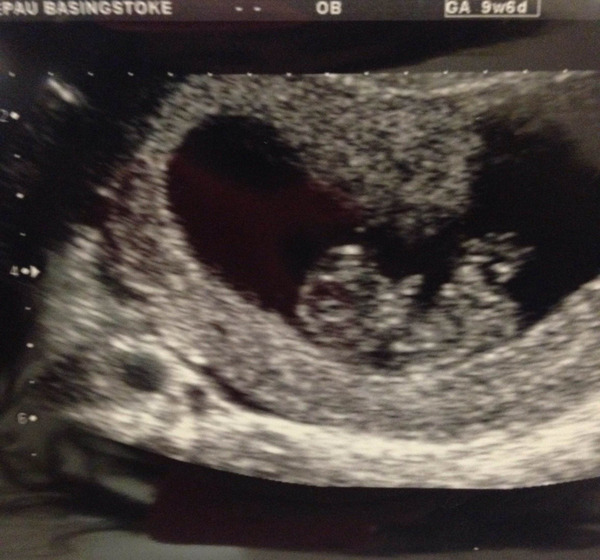

QforCucumber · 19/08/2015 17:33

Rosie mine was at 9+1 and showed this, says 2.7cm in the details.

Nhs scan is on 7th sept, I'll be 13+1 I think, can't wait!

Lovely scan pictures Q, maybe and rosie they're all so clear!

This is my scan from last Tuesday when I was 9+2. Seems like just a wee blob compared to others I've seen. My own date had me at 9+1 but scan shows 9+2. They've said they will confirm dates at 12 week scan which is 2 weeks today and really not coming quick enough!